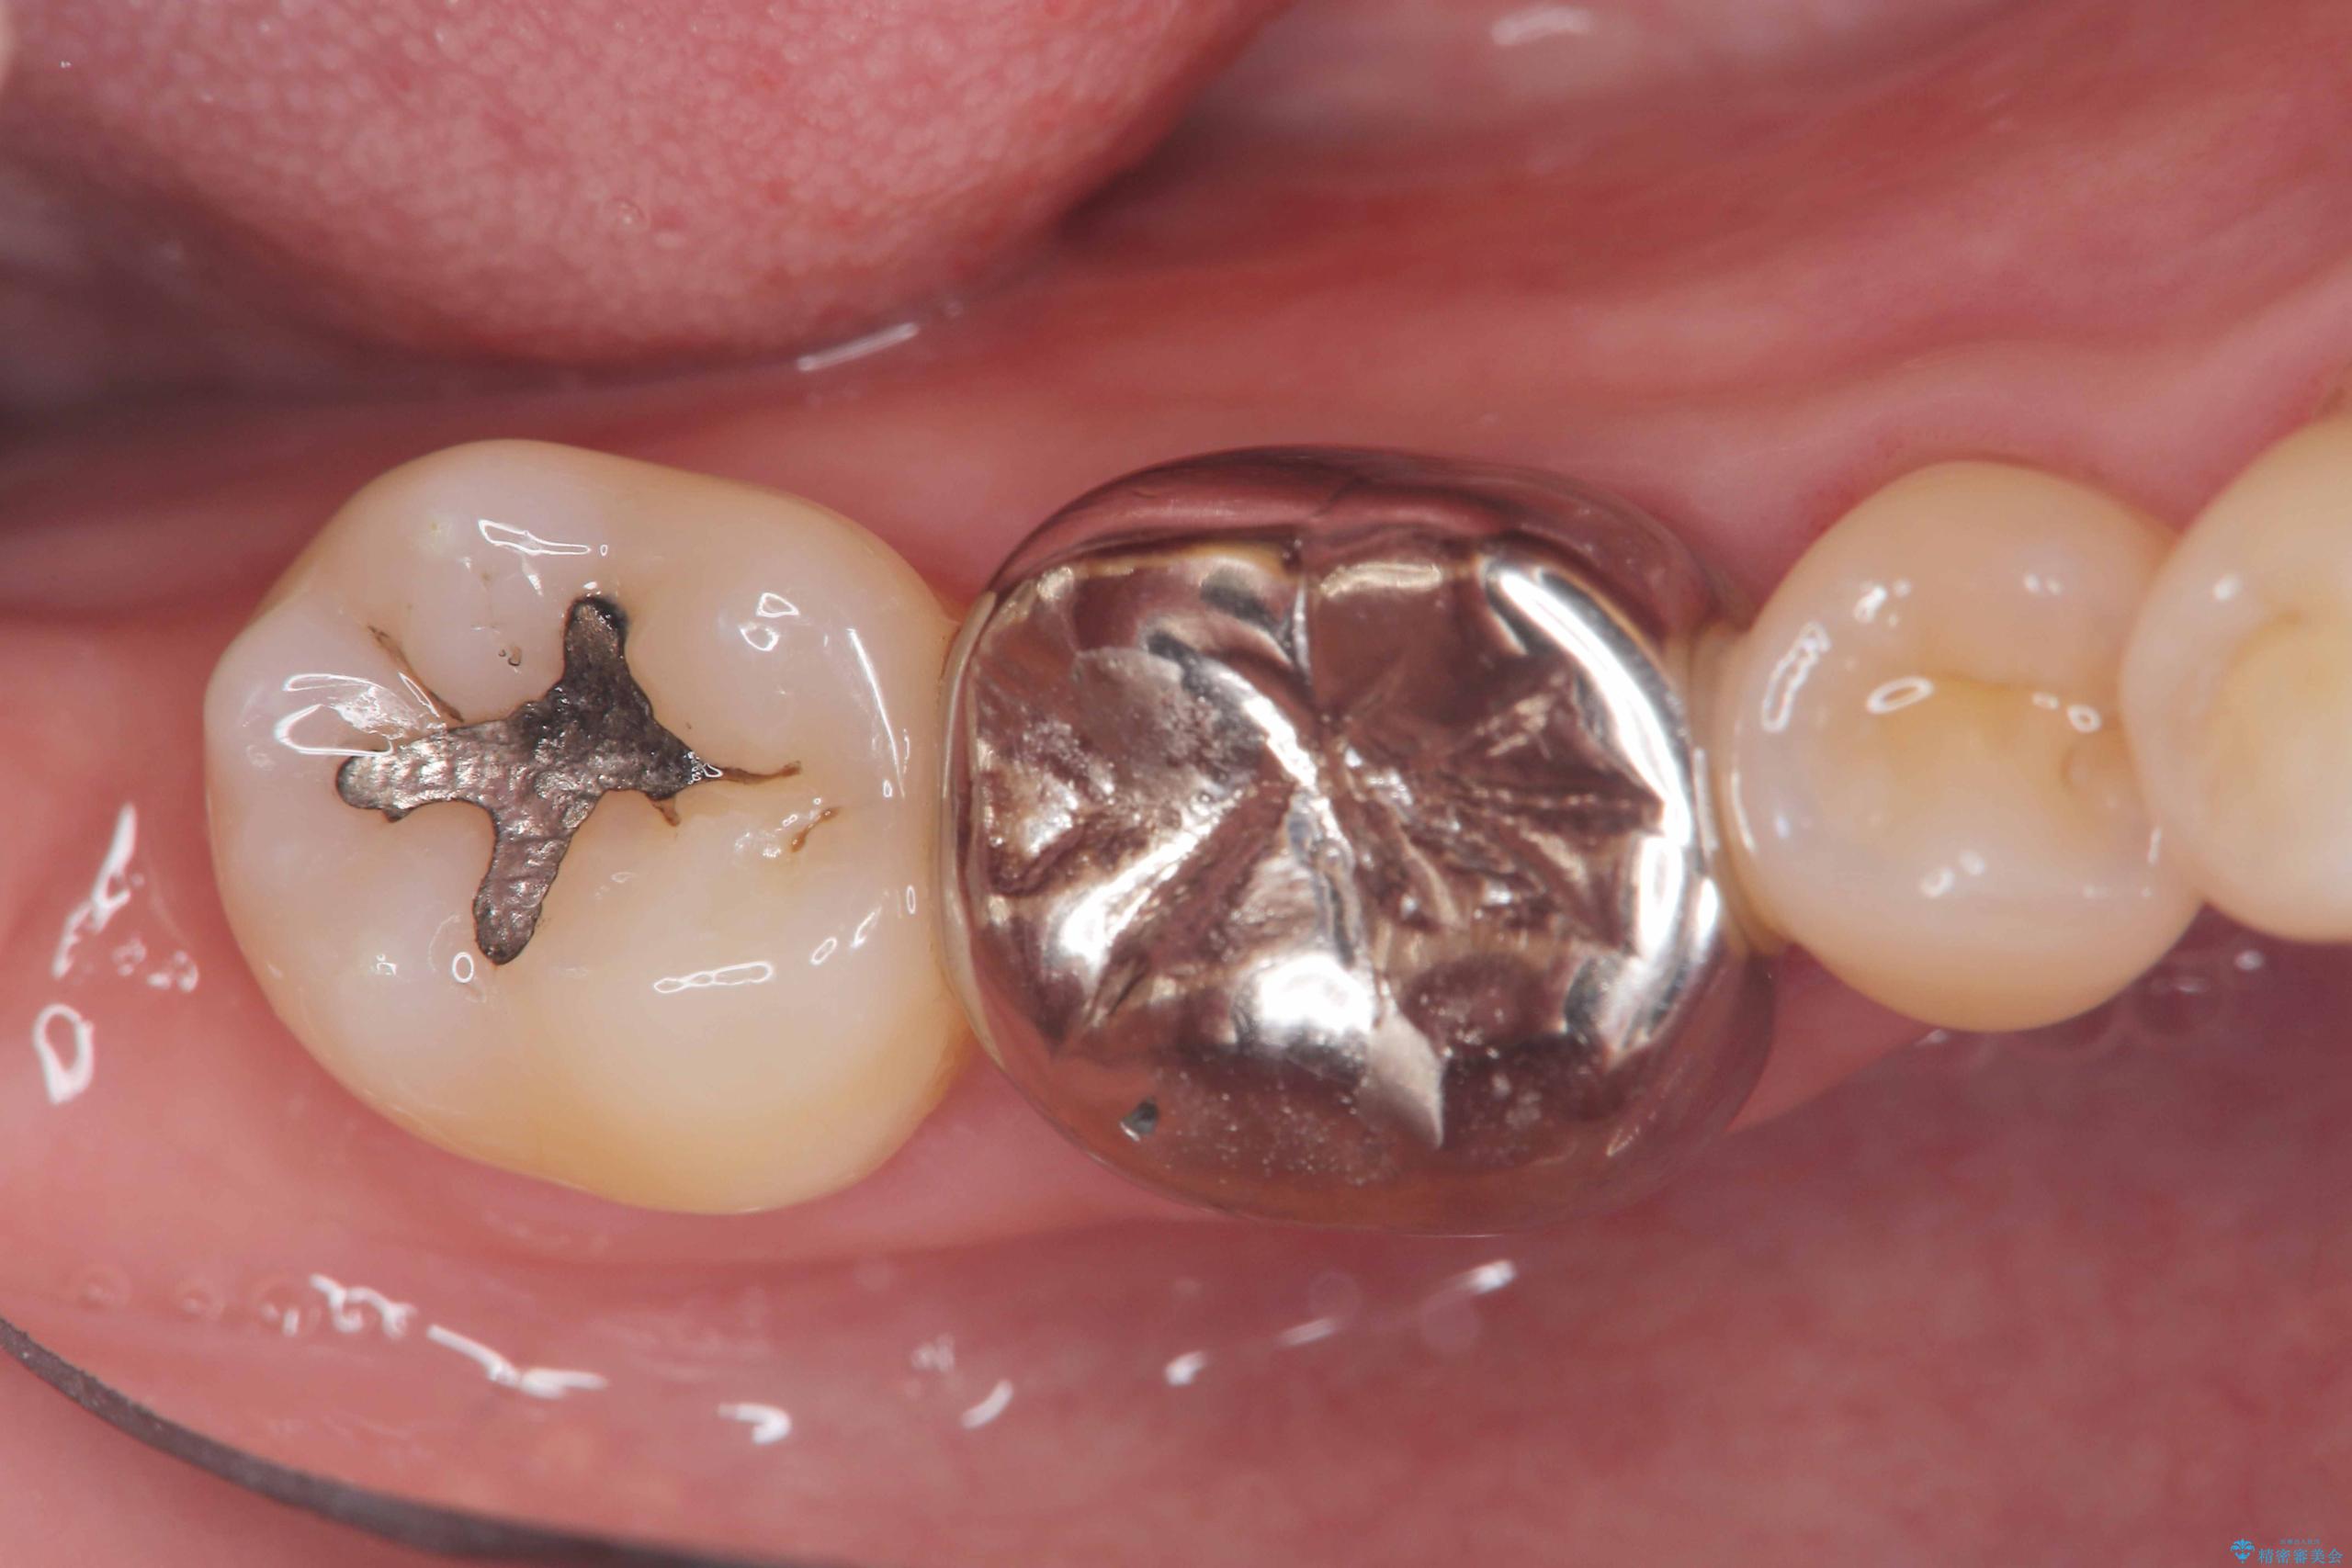

- 「銀歯を白くしたい」を主訴に来院された患者様です。銀歯を外し虫歯を除去後、オールセラミッククラウンで治療を行いました。

銀歯を外して内部の虫歯を丁寧に除去した後、オールセラミッククラウンにて修復を行いました。審美性と機能性の両面で改善が得られ、患者様にもご満足いただきました。